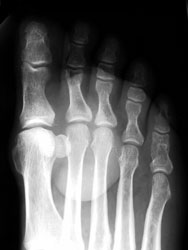

Epidermal inclusion cysts are most commonly associated with trauma, in superficially situated bones such as the calvarium, phalanx, hand, and foot. They are caused by implantation of epithelium under the skin, forming cysts with secondary bone erosion. Pain over the lesion is common. A well-defined mass is usually noted on plain radiographs. There is no associated periosteal reaction, or soft tissue swelling.

47 year old male with a 6 x 3.5 cm lobulated mass along plantar medial aspect of the 1st toe, which is hypointense on T1W and hyperintense On T2W images. Scattered small foci of hypointensity, representing calcifications is present on all the sequences. The soft tissue mass with small calcifications is also seen on the plain radiograph.